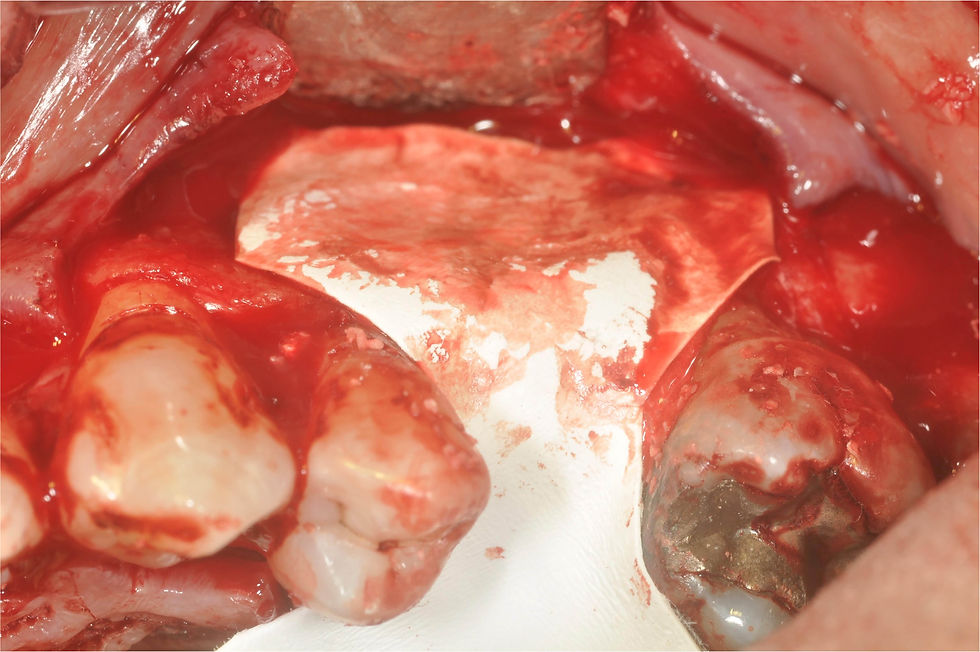

Bone regeneration obtained by a combination of autologous bone and deproteinized bovine bone mineral (DBBM), added with amoxicillin.

Relaxation incisions to obtain a coronal repositioning of the flaps that does not apply tension to the underlying regeneration process.